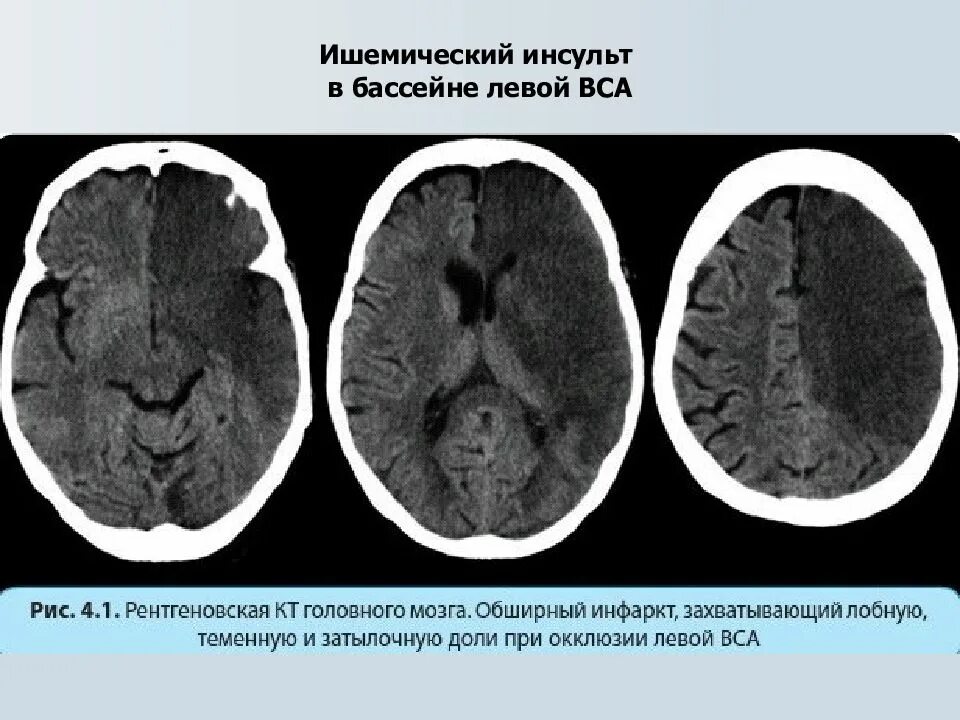

Онмк в бассейне сма